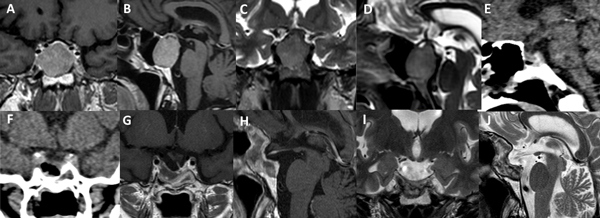

La técnica de “Guante Blanco” se indica en pacientes con macroadenomas no funcionantes, apoplejía pituitaria, enfermedad de Cushing, acromegalia, adenoma secretor de TSH y en portadores de prolactinomas con una clara indicación quirúrgica. La indicación principal es en tumores infradiafragmáticos, es decir, por debajo de la duramadre del diafragma selar o respetando el orificio del anillo dural (Figura 5). Se podría valorar a futuro su indicación en casos con extensión supraselar sin invasión ventricular y sin invasión lateral.

Existen situaciones que contraindican relativamente el uso de esta técnica y precisa un abordaje “extendido”: adenoma en reloj de arena, alto grado de extensión supraselar (e.g. invasión del III ventrículo), extensión para-selar (e.g. englobamiento carotideo), consistencia dura o fibrosa del tumor (Figura 6).

Figura 5. Paciente de 45 años con prolactinoma infradiafragmático resistente a cabergolina. Se utilizó un abordaje de Guante Blanco para su tratamiento. A-D: RM preoperatoria. E-F: TC del primer día postoperatorio. G-J: RM postoperatoria.